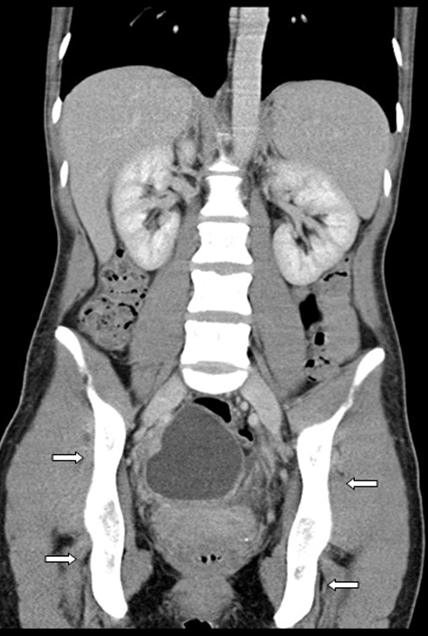

A 41-year-old female, para 2, admitted to hospital for right iliac fossa pain, plus reduced appetite and weight loss, that had been present for two months. Furthermore, the patient had generalized tenderness in lower abdomen. Observations showed normal blood pressure and pulse, but raised temperature of 37.8°C. Computed tomography scan revealed bilateral predominantly cystic ovarian masses with solid component, plus multiple peritoneal nodules with pelvic free fluid (Figure 1) and (Figure 2). Ultrasound of the abdomen and pelvis showed a normal-sized anteverted uterus with an IUCD in situ within the endometrial cavity. It confirmed earlier CT scan findings regarding bilateral complex adnexal cysts; measurements were 70x63x61 mm (right) and 63x48x54 mm (left). The right ovary was separate from the cyst, but the left ovary was not separate from the adnexal cyst. White cell count and C-reactive protein results were only slightly raised 13x109/L and 119 mg/L respectively, and tumor markers CA125, CEA and CA19-9 were normal.

Figure 2: Coronal computed tomography scan of patient, upon admission to hospital. Infection has spread bilaterally in the ovaries and large areas of the pelvis.